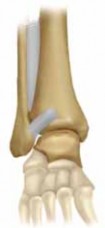

1. Direct access to the posterior malleolus fracture (

TECH FIG 5A

) can be obtained through the posterolateral approach to the fibula (

TECH FIG 5B

).

1. The interval between the Achilles and the peroneal muscle is developed (

TECH FIG 5C

2. The flexor hallucis longus is taken off the fibula down to the interosseous membrane, and then the rest of the deep posterior compartment is taken off the posterior tibia (

TECH FIG 5D

TECHNIQUES B TECH FIG 5 • Direct posterior plating is well

---

C

suited for fractures involving large portions of the posterior malleolus.

A.

Postreduction lateral radiograph showing a posterior malleolus fracture involving more than one third of the articular surface.

B.

Patient in prone position, incision between Achilles and posterior fibula border.

C.

Access is via the interval between the flexor hallucis longus and the peroneal muscle belly. D. Posterior malleolar fragment following A D fibular plating. POSTERIOR MALLEOLUS FIXATION 1. If an adequate reduction can be achieved via closed, indirect reduction, the fracture can be stabilized with cannulated lag screws placed in the anterior-to-posterior direction.